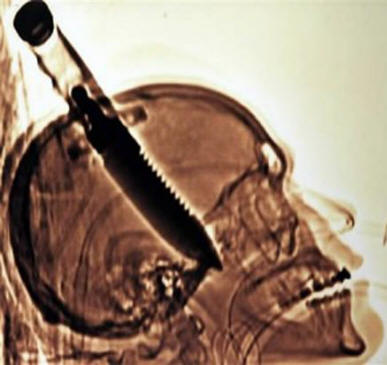

Leta 1998 je Michael Hill obiskal prijatelja s Floride, ko je nenadoma na ulici do njega pobegnil norček in … brez razloga brez razloga ga je zataknil v goli nož. Michael je prišel domov, kajne z ročajem, ki mi štrli iz glave, in tam sem samo šokiran prijatelj poklical rešilca. Kasneje je Hill to rekel skoraj ni čutil bolečine v glavi (čeprav je tomografija to pokazala nož je prodrl v možgane za približno 20 cm!), edino kar je opozoril, da je to “vročina v desnem očesu.” Po štirih urah operacije Michael je bil že premeščen v oddelek in nekaj dni kasneje izpraznjen. Na koncu je bila fantina leva roka paralizirana, toda zdravniki pravijo, da se je še vedno zlahka spustil.